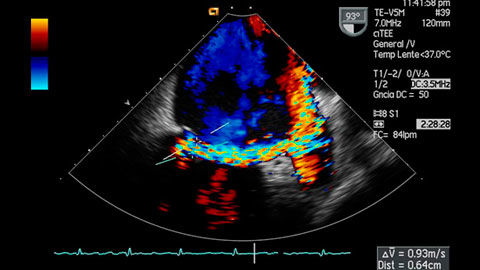

1. La Ecocardiografía.